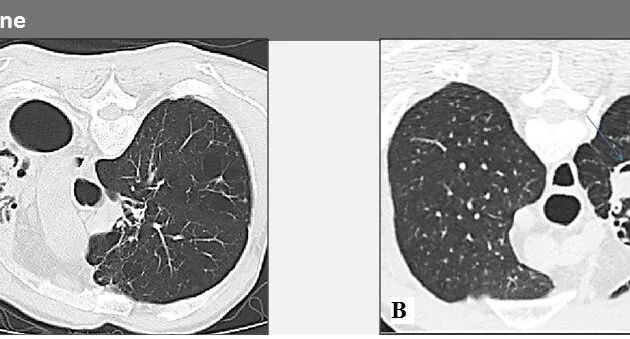

放射学(图10、11、12):

1、长期肺部阴影。

2、在一个或两个上叶中具有渐进空化的结节。

3、非特异性,最常见的是模仿分枝杆菌感染。

4、病变更外周,伴有胸膜增厚,可能形成支气管胸膜瘘。

图11:慢性坏死性肺曲霉菌病。轴向CT显示实变和结节的局灶区域被磨玻璃改变的光环包围。

图12:慢性坏死性肺曲霉菌病。MDCT扫描显示病变的演变,其大小增加并显示出中心空洞的区域。